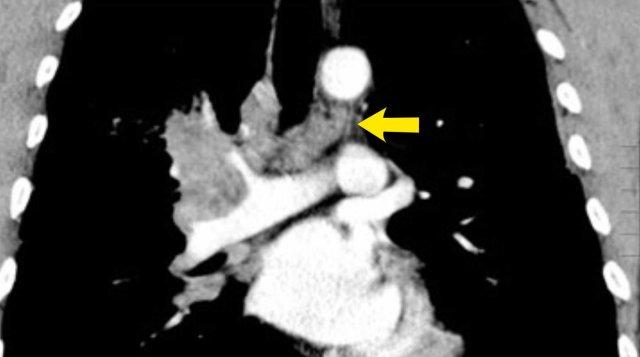

Khối u bên phải với di căn hạch N3, bao gồm các trạm trung thất đối bên 4L và 5.

Các hình ảnh này thuộc về hai bệnh nhân khác nhau bị ung thư phổi ở phổi phải.

Hình ảnh của một bệnh nhân có khối u bên phải.

Có các hạch N3 ở phía đối bên và ở vùng thượng đòn phải.

Cuộn qua các hình ảnh để xem.